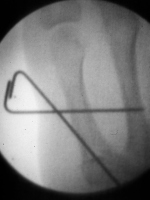

| Freer elevator

introduced percutaneously as a reduction aid. |

| Percutaneous

fracture stabilization with three pins via the

dorsal radial tubercle, radial styloid and FCR

portals. |